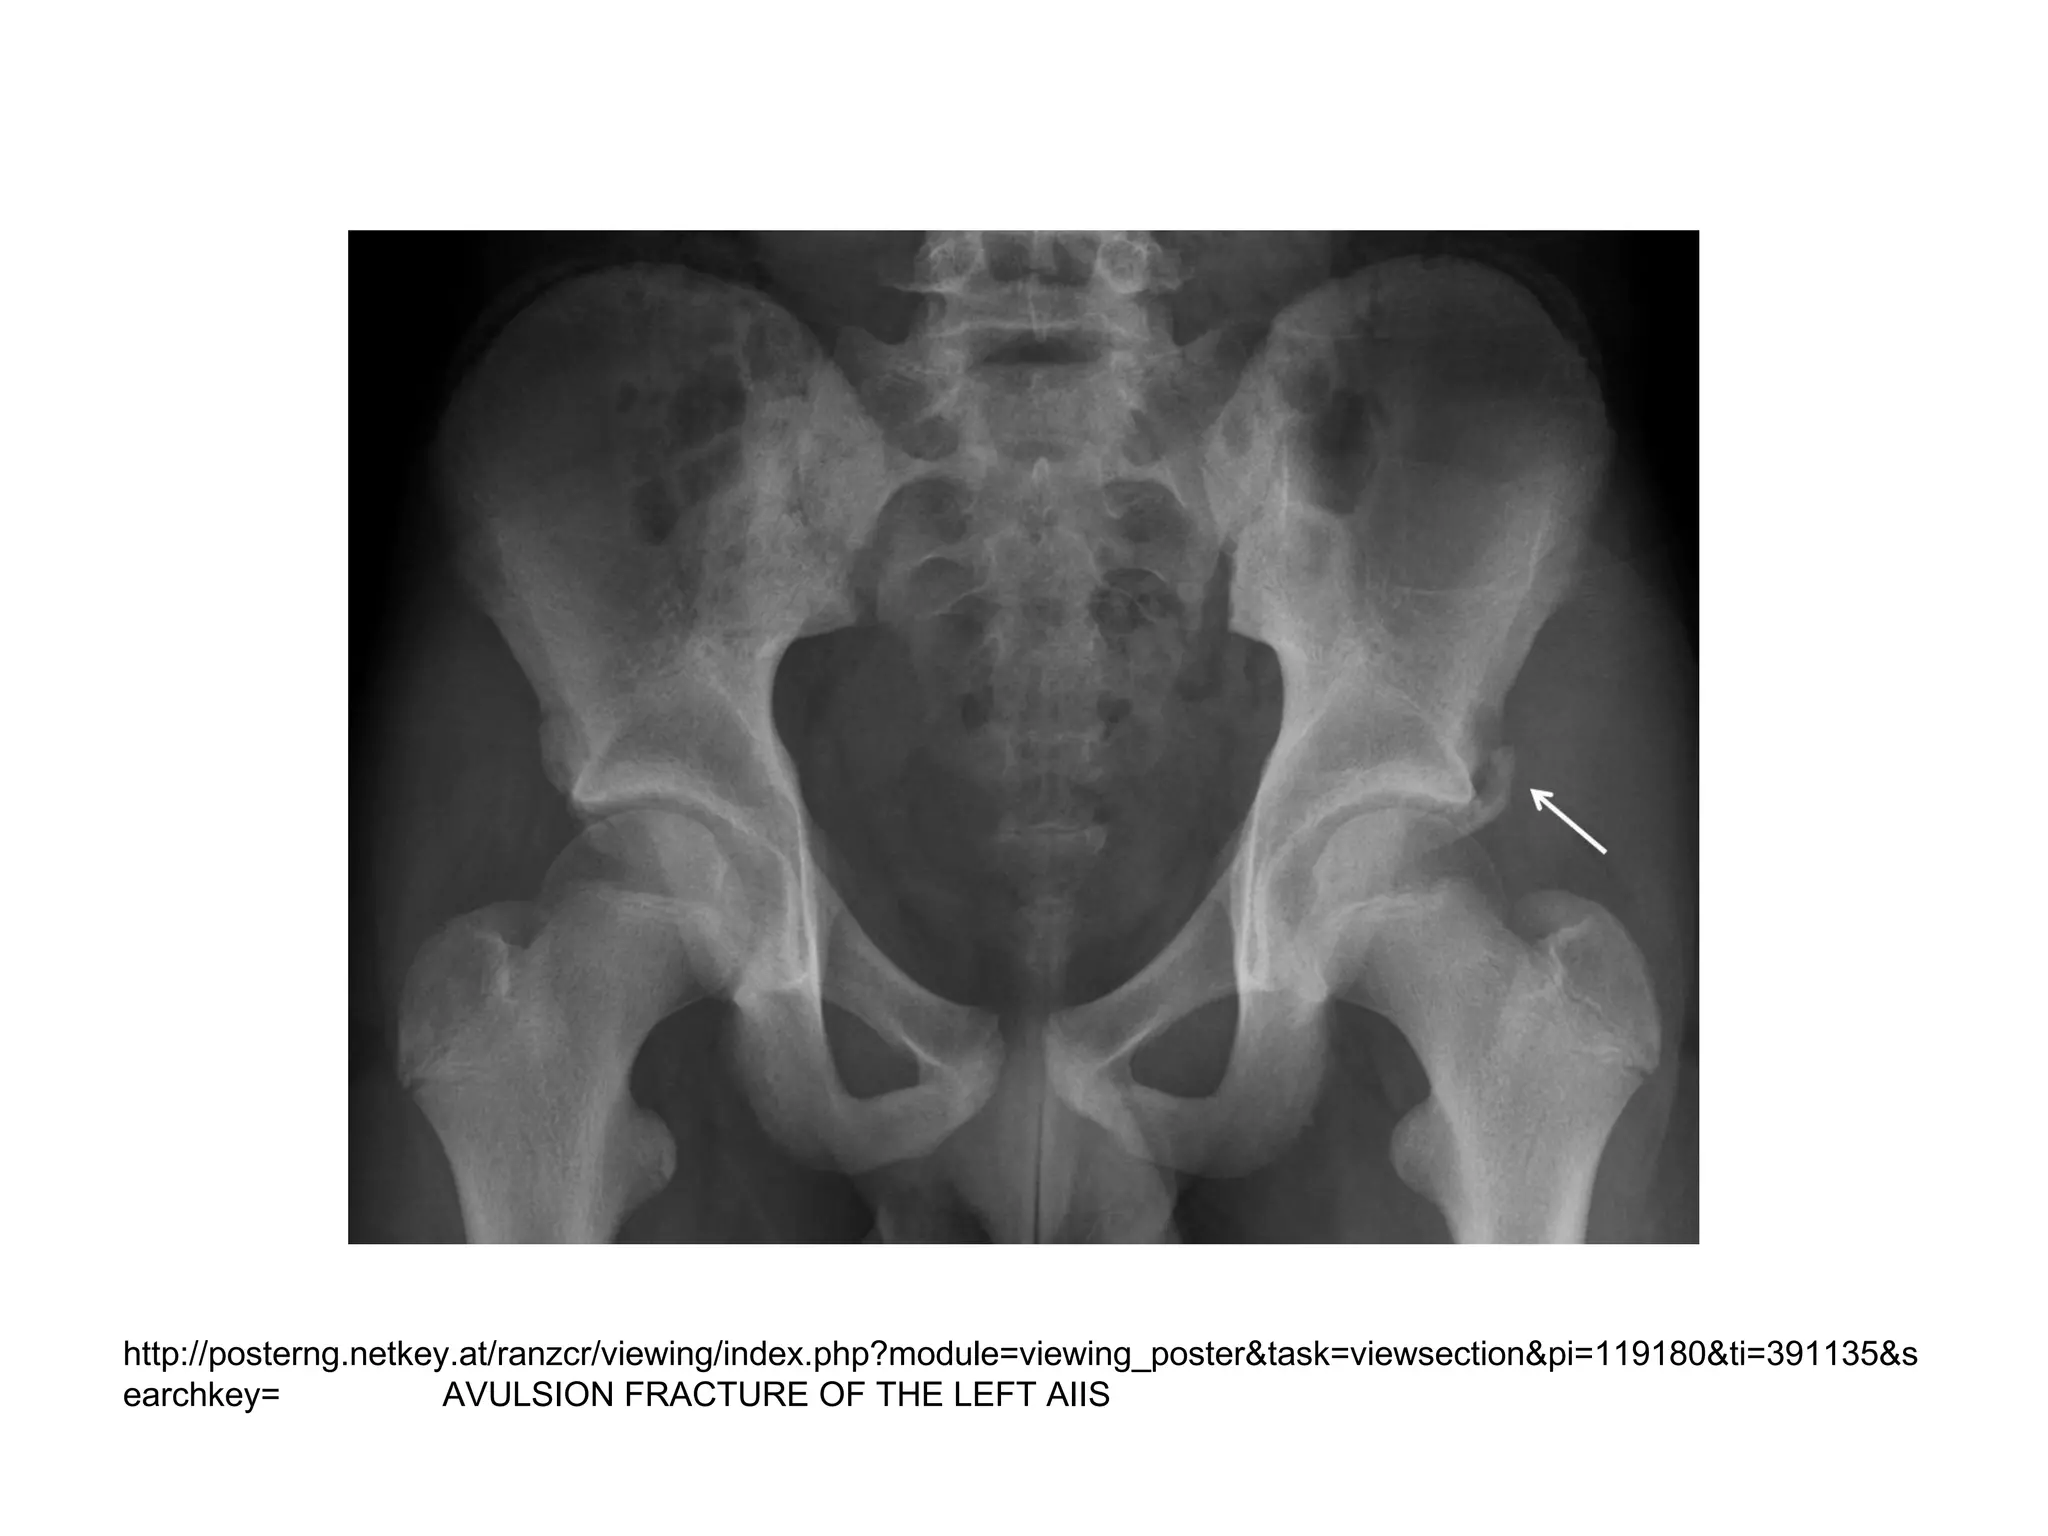

Exposure

• Pack a gauze sponge on the inner and

outer cortices to facilitate subperiosteal

dissection and provide hemostasis

• Expose the anterior inferior iliac spine

(AIIS) by elevating the periosteum with the

hip abductor muscles from the outer cortex

of the ilium until the AIIS is clearly defined

http://posterng.netkey.at/ranzcr/viewing/index.php?module=viewing_poster&task=viewsection&pi=119180&ti=391135&s

earchkey= AVULSION FRACTURE OF THE LEFT AIIS